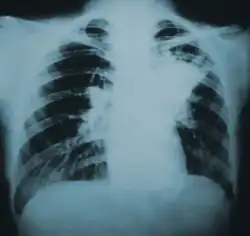

| Lung infiltration in blastomycosis. | |

Blastomycosis manifests as a primary lung infection in about 79% of cases.[8] The onset is relatively slow, and symptoms are suggestive of bacterial pneumonia, often leading to initial treatment with antibacterials. Because the symptoms are variable and nonspecific, blastomycosis is often not even considered in differential diagnosis until antibacterial treatment has failed, unless there are known risk factors or skin lesions.[8] The disease may be misdiagnosed as a carcinoma, leading in some cases to surgical removal of the affected tissue.[19] Upper lung lobes are involved somewhat more frequently than lower lobes.[20] If untreated, many cases progress over months to years to become disseminated blastomycosis.

Blastomycosis in the lungs may present a variety of symptoms, or no symptoms at all.[8] If symptoms are present they may range from mild pneumonia resembling a pneumococcal infection to acute respiratory distress syndrome (ARDS).[8] Common symptoms include fever, chills, headache, coughing, difficulty breathing, chest pain, and malaise.[8] Without treatment, cases may progress to chronic pneumonia or ARDS.[8]